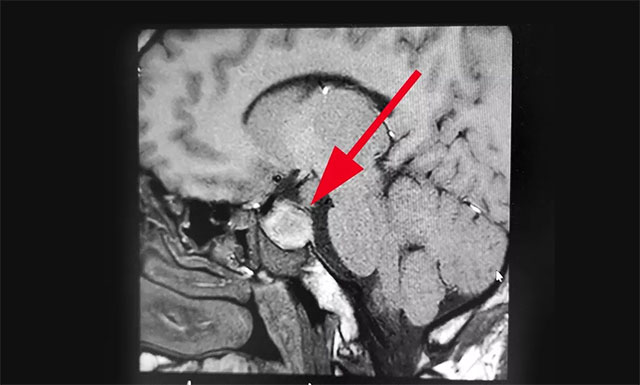

入院時(shí),患者已經(jīng)連續(xù)9天陣發(fā)性頭痛,經(jīng)檢查其左側(cè)眼瞼有輕微下垂,約1米距離時(shí)有視物重影等癥狀,雙眼視力0.2,四肢指關(guān)節(jié)較之前變粗大。針對患者情況,6B病區(qū)主任潘仁龍基于多年臨床經(jīng)驗(yàn)立即作出判斷,急行頭顱鞍區(qū)MRI平掃+增強(qiáng),顯示:蝶鞍顯著擴(kuò)大,鞍底下陷,鞍區(qū)見一不規(guī)則腫塊,大小約1.6*3.2*2.1cm,病變向周圍生長,突入鞍上池,推移視交叉,向下生長,鞍底受壓,向鞍旁生長,海綿竇推擠改變。

▲ 術(shù)前影像:垂體大腺瘤,超蝶鞍生長,侵襲海綿竇

由潘仁龍主任、李士其教授、吳治群博士組成的專家組指出,根據(jù)患者影像學(xué)檢查及檢驗(yàn)結(jié)果分析,患者考慮為垂體大腺瘤伴卒中,患者面容有改變,懷疑為生長激素腺瘤。腦垂體瘤腺瘤出血,壓迫了視網(wǎng)膜及海綿竇內(nèi)的動眼神經(jīng),導(dǎo)致動眼神經(jīng)麻痹,視物重影。